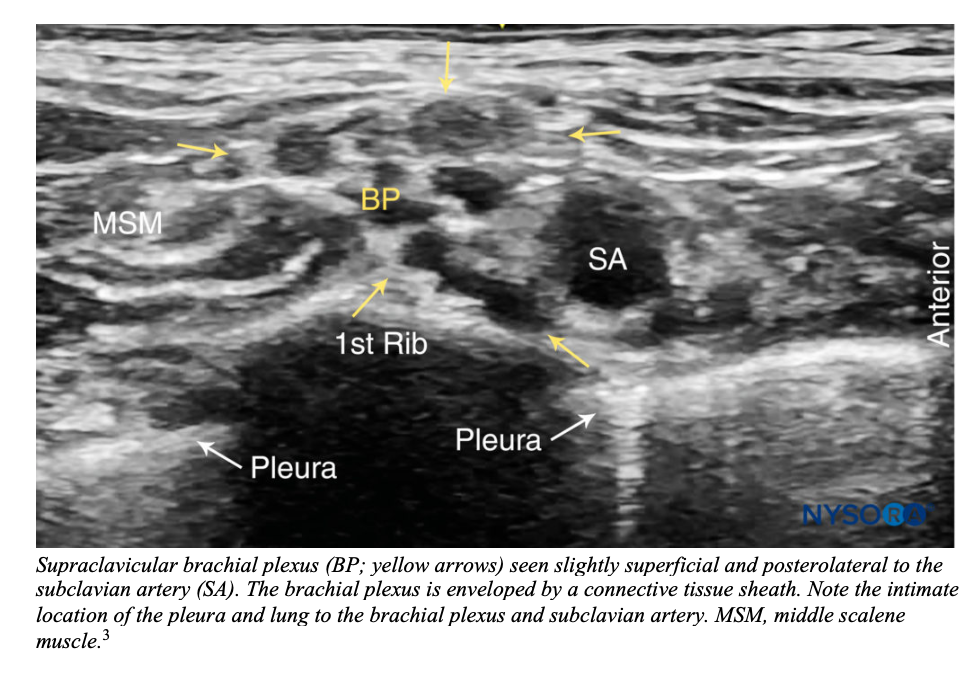

Identify the subclavian artery as an anechoic pulsating structure. The brachial plexus is seen immediately superior and posterior-lateral to the artery as a group of small hyperechoic circles with hypoechoic centers (honeycomb appearance). Obtain the view where the brachial plexus is traversing over the first rib. Hyperechoic pleural lines should be seen anterior and posterior to the first rib.3-4

Subclavian vein is inferior-medial to the subclavian artery but may not always be visualized.4

Be aware that other vessels (dorsal scapular artery, transverse cervical artery, suprascapular artery) can sometime traverse in the vicinity or through the brachial plexus. Be sure to fan through the supraclavicular fossa and use color doppler often to identify these vessels.3